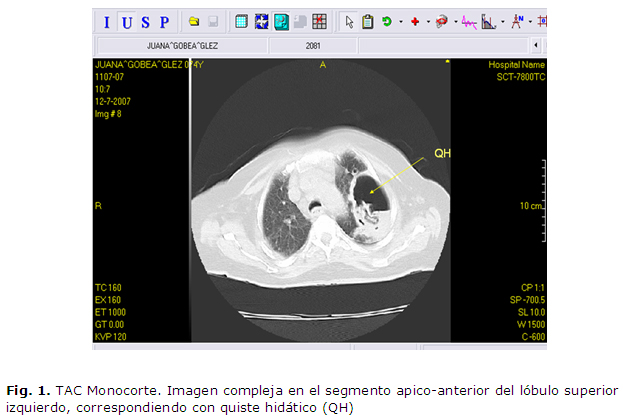

Se le realizó una radiografía de tórax, observándose la presencia de imagen radio opaca del tamaño de una moneda en el lóbulo superior del pulmón izquierdo, que se interpretó como una posible neoplasia pulmonar; en el resto de los complementarios se encontró una discreta eosinofilia y cifras de hemoglobina disminuidas. En un periodo de nueve días se le repitió la radiografía de tórax y se observó que la imagen había aumentado significativamente de tamaño, por lo que se decide realizar una tomografía axial monocorte, observándose en el segmento apicoanterior del lóbulo superior izquierdo una imagen compleja de 87x62 mm de diámetro y con nivel hidroaéreo en su interior; por encima del nivel se visualiza una imagen redondeada de 53 UH, que varia desde 53-92 UH en relación con la imagen sólida que contenía aire en su interior, y membranas desprendidas en su interior. Se observó el bronquio de drenaje a la lesión principal, el resto del parénquima de ese lado presentaba áreas de hiperventilación bronquiectasias y signos de fibrosis pulmonar. Después de analizar dicho resultado y ante la atípica evolución de la lesión se duda del diagnóstico inicial y comienza una revisión sobre el tema, después de la cual el colectivo llegó al consenso que debido a que la paciente habitaba en una zona rural donde convivía con abundantes perros, carneros y otros animales, además, en muy malas condiciones higiénico sanitarias y de tener cierto grado de inmunosupresión por su enfermedad renal crónica, presentaba además un nódulo pulmonar característico, por todo lo cual se plantea el diagnóstico de hidatidosis pulmonar.

La paciente fue evaluada con frecuencia mensual evidenciándose una paulatina disminución del tamaño del quiste hidático. (Ver figuras 1, 2, 3)